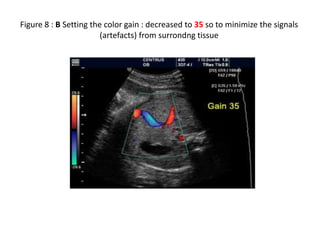

Figure 8 A & B : Setting the color gain to minimize the signals (artefacts) from

surrondng tissue.. A (Color gain is 71 with tissue artefacts)

Figure 8 : B Setting the color gain : decreased to 35 so to minimize the signals

(artefacts) from surrondng tissue

Figure 8 A& B : Setting the color gain to minimize the signals (artefacts) from surrondng tissue.. A (Color gain is 71 with tissue artefacts)

Figure 8 :B Setting the color gain : decreased to 35 so to minimize the signals (artefacts) from surrondng tissue